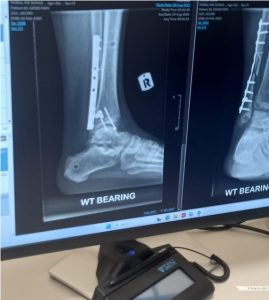

That dream was abruptly interrupted by a serious workplace accident that left Suman with a broken leg. Months of immobility followed. With unpaid medical leave wages and an ongoing injury compensation process, he has been left without income. The basic provisions he initially relied on have since ceased. āThey didn’t pay insurance, it’s not my fault,ā Suman said quietly. āThey never thinking I have family, I have baby.ā

Today, Sumanās leg has only about 40 percent functionality. Even if it fully heals, he knows he may no longer be able to carry heavy loads, making a return to construction work uncertain. āMy future plan has died. When I ok I also donāt know,ā he admitted, describing the uncertainty he now lives with.